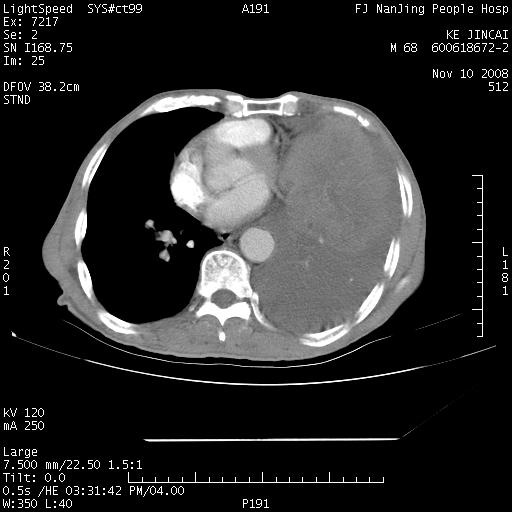

是个很有看头的病例,咋人气那么不旺?没多少人兴趣呢?这个病例几大怪:1   恶性肿瘤侵犯心肌左房怪,心肌一般不会被恶性肿瘤侵犯吧?2   左下肺均匀实变怪,内无含气,有别一般不张实变,含气肺泡完全为液体取代,而非一般不张实变的肺萎陷,冷不丁还以为是肿大的脾脏3   肿瘤本身怪,像tb肺不张4   这么有看头的病例没人气怪。呵呵。

左肺恶性肿瘤侵犯肺动脉,左心房内瘤栓,胸膜转移。

左肺恶性肿瘤侵犯肺动脉,左心房内瘤栓,胸膜转移,少见,学习了。